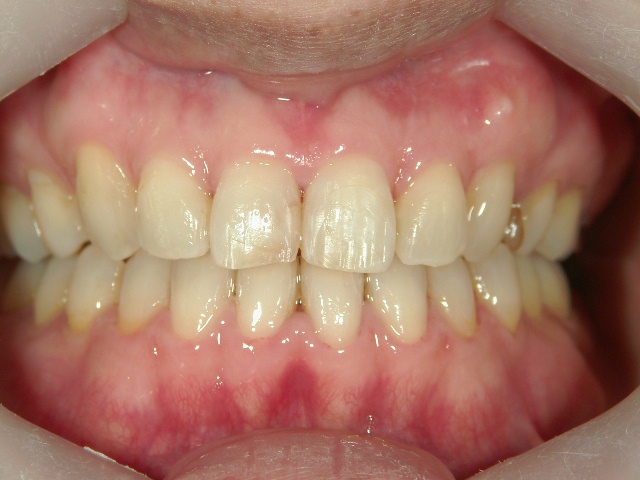

矯正歯科(全顎ワイヤー矯正)治療後

矯正歯科 治療後